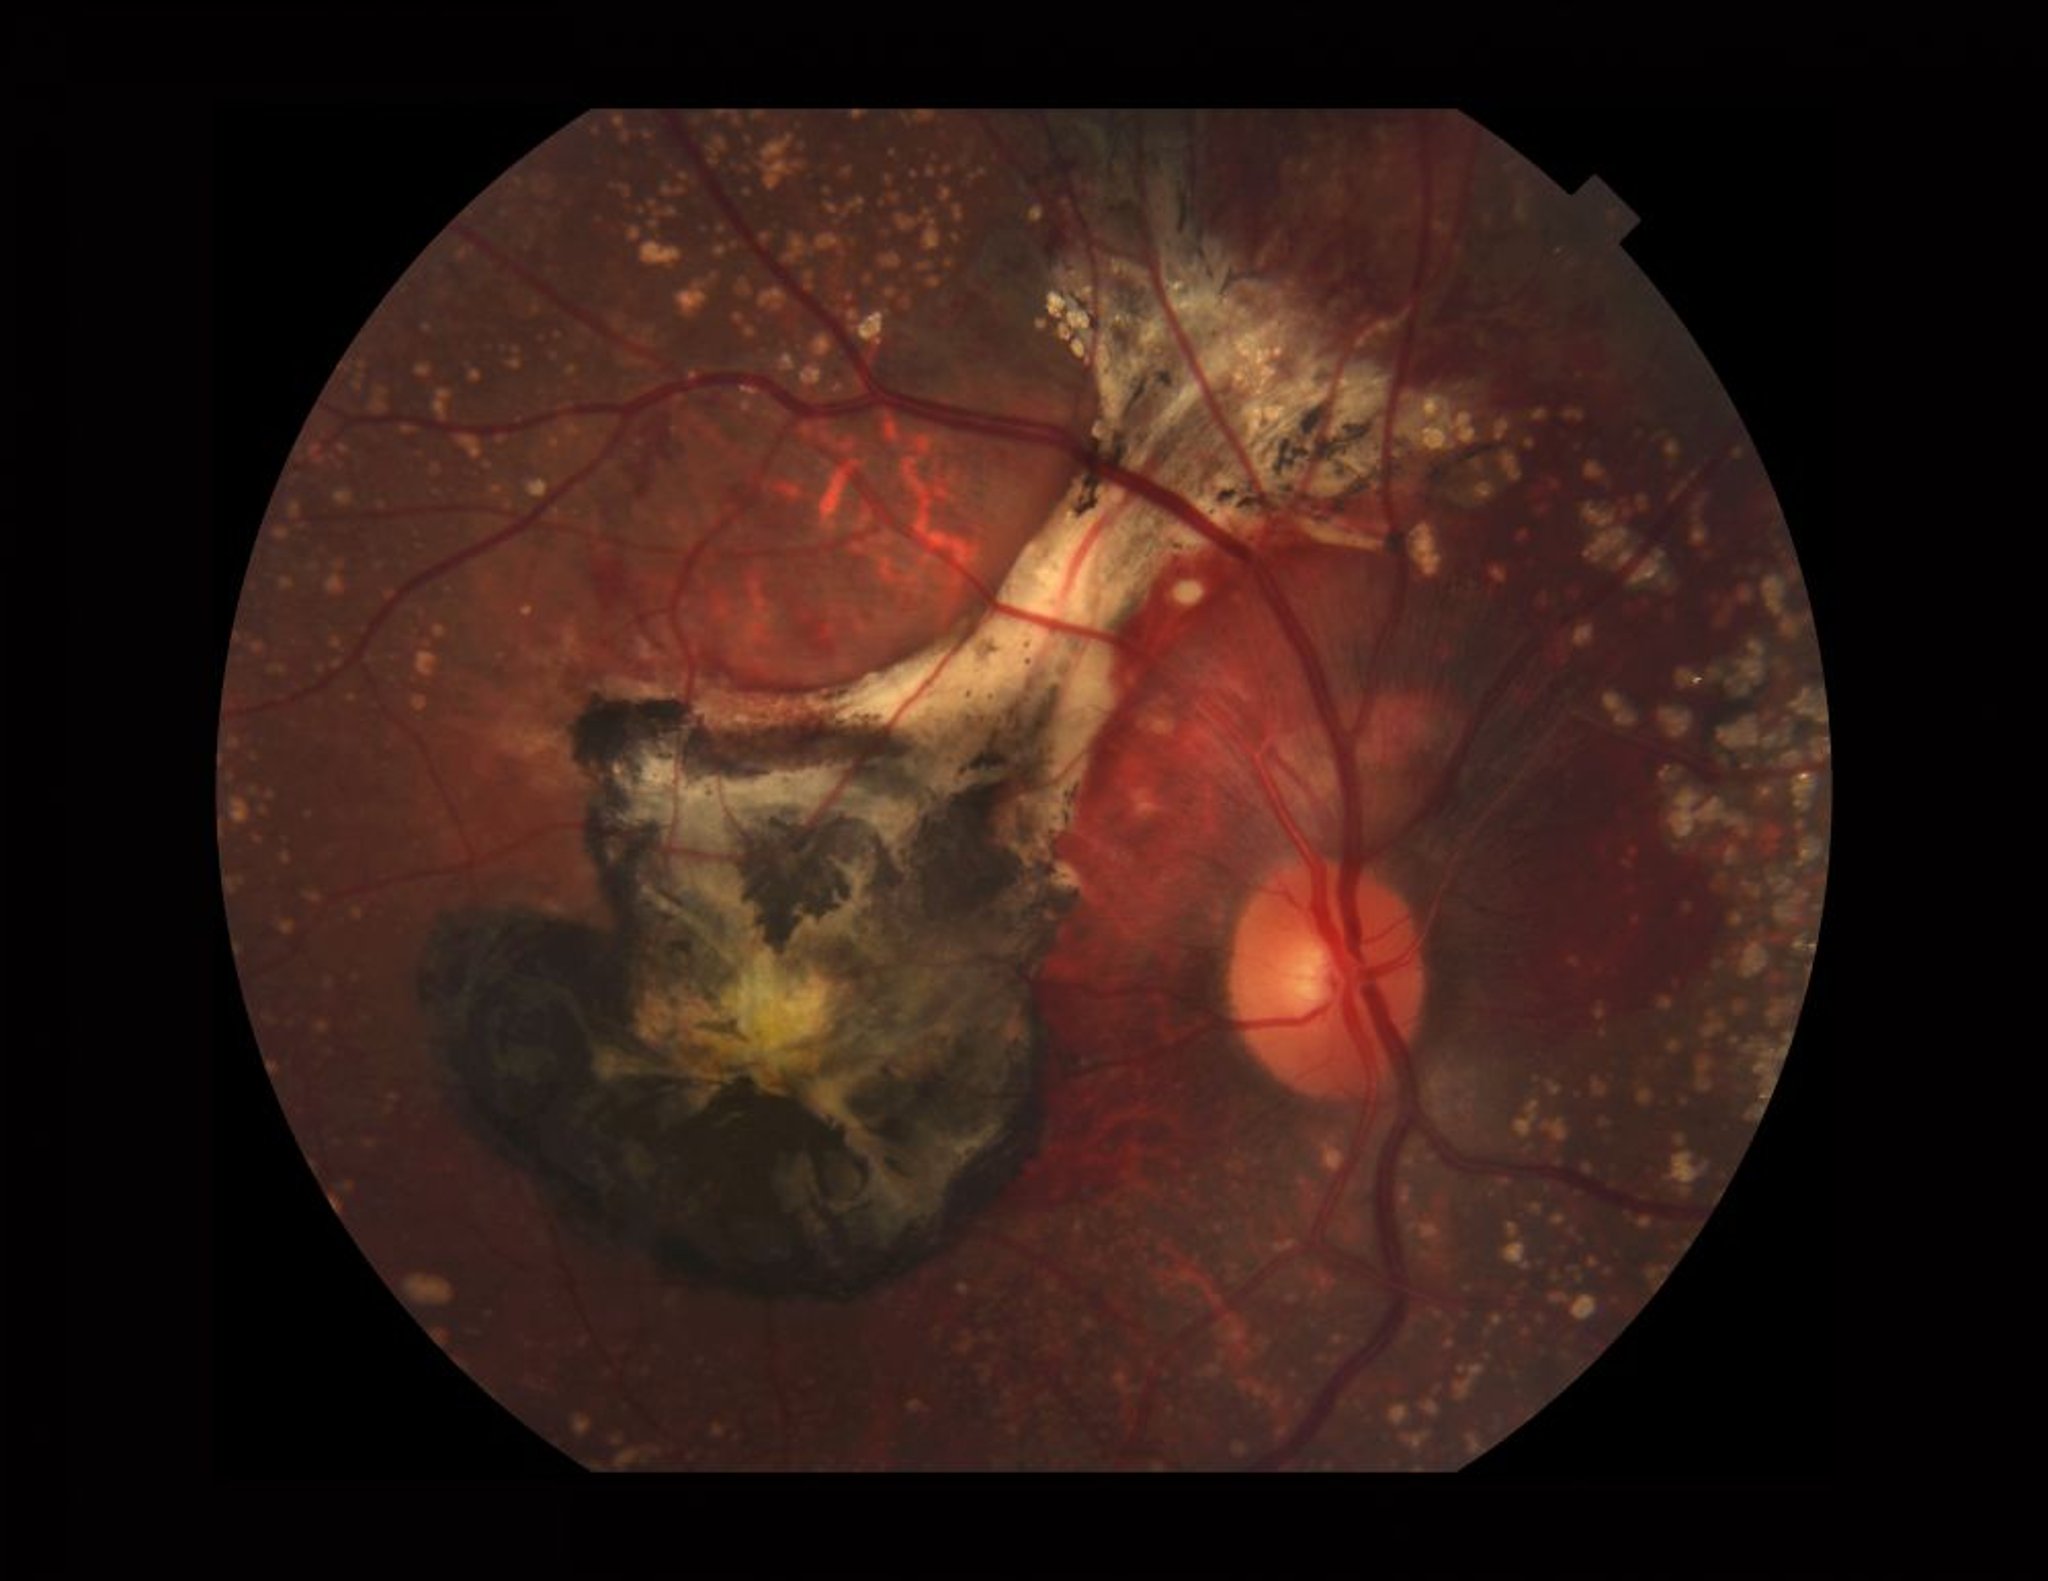

Altersabhängige Makuladegeneration (feuchte)

Foto einer Netzhaut, die von feuchter AMD betroffen ist. Dieses Bild zeigt verkalkte Drusen, subretinale Blutungen, eine choroidale neovaskuläre Membran (schwarz von altem Blut und Fibrose) und Xanthophyll (gelb)-Pigment in der Makula.

PAUL WHITTEN/SCIENCE PHOTO LIBRARY